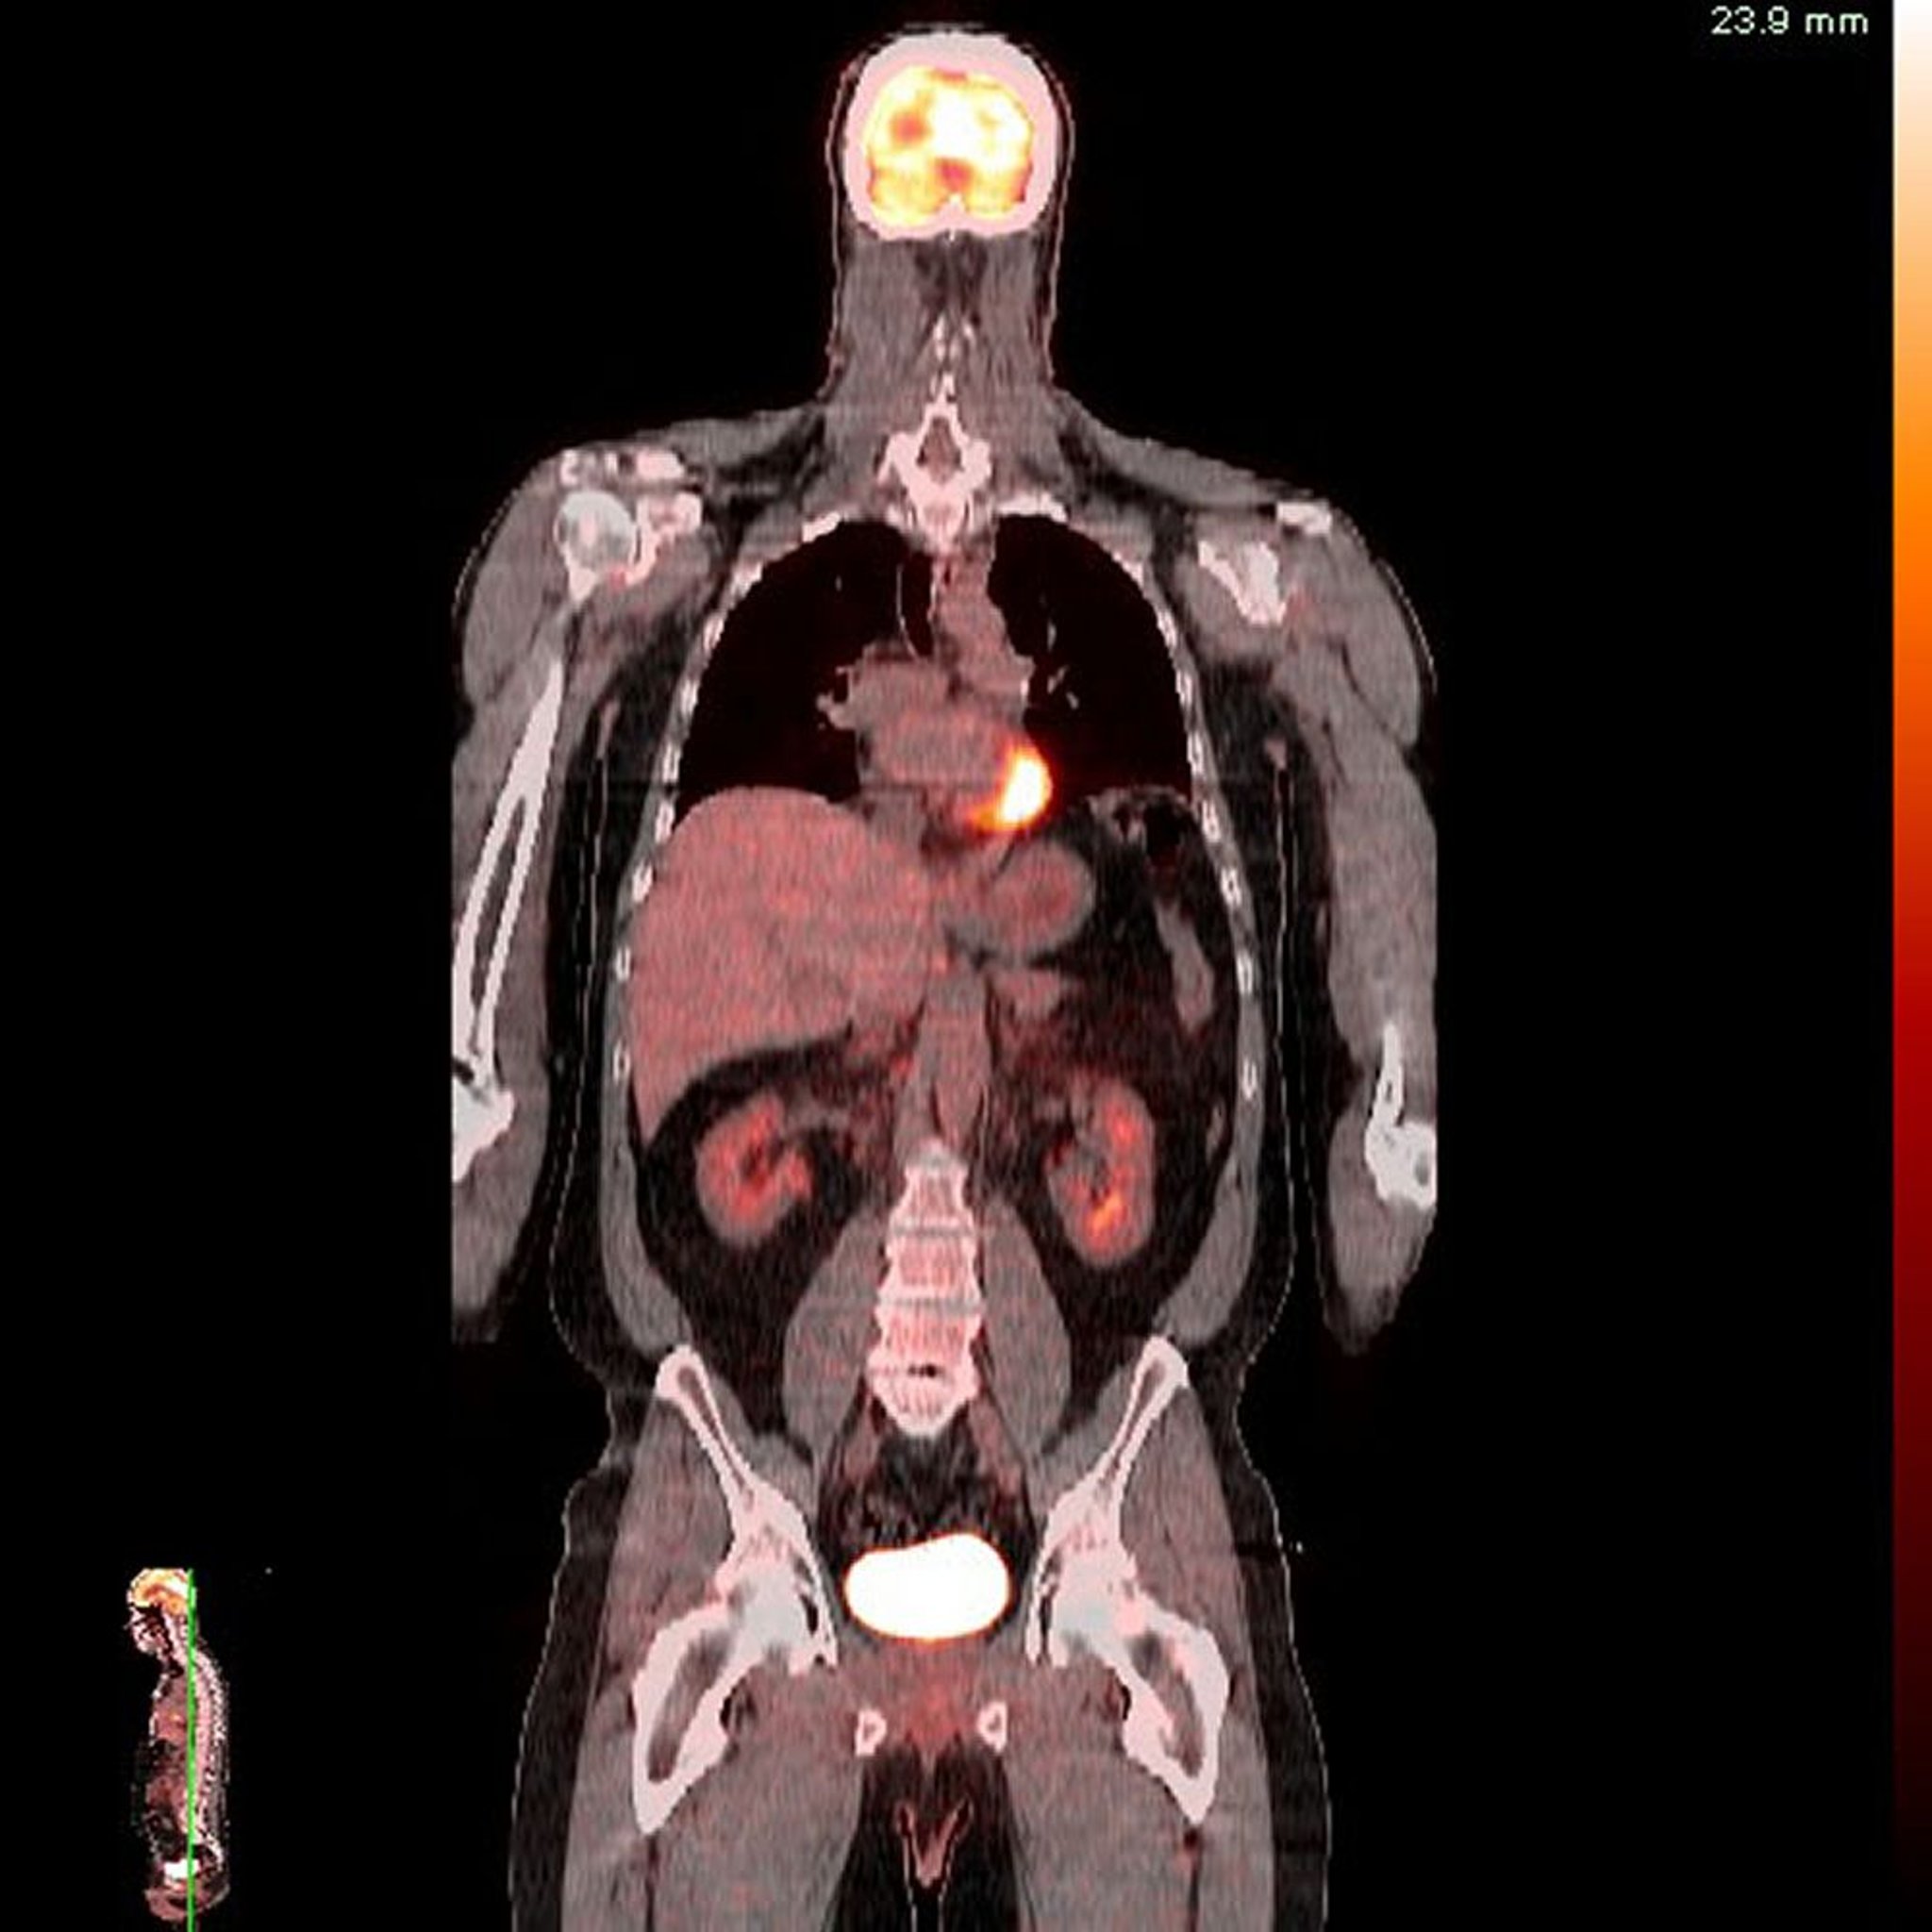

Tomografía por emisión de positrones-Tomografía computarizada (PET-TC)

Imagen proporcionada por Jon A. Jacobson, MD.